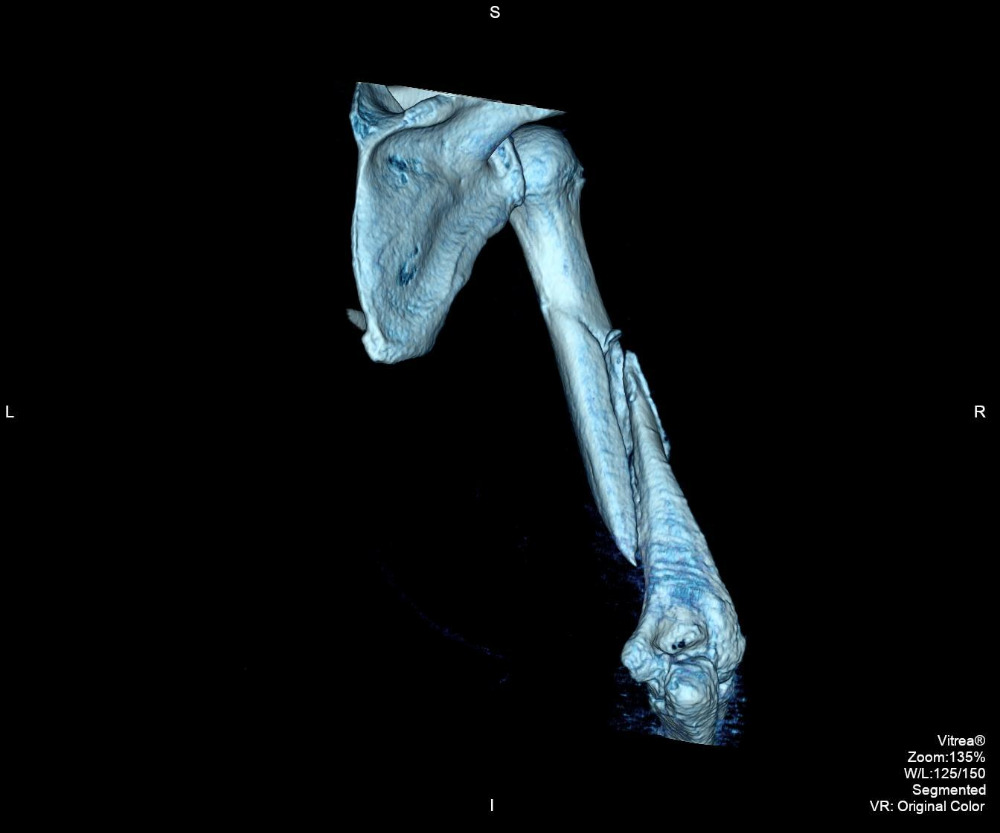

I had my surgery on September 13th, 2016. According to the doctor, it was" very, VERY BAD!" He had to find the nerve buried within the fracture. Carefully move it out of the way before he could clean up the debris of the broken bones. The bicep muscle was caught between the fractures. He had to recut the bone to straighten it out, place a twelve inch long, metal plate with a dozen screws, to hold it all in place. The over two year wait didnt do me any favors. I now have a long healing process and eventually physical therapy. Meanwhile, I no longer have living benefits and I desperately need your continued help. I need to raise a minimum of $4,000 to survive through January 2017. Anything will help, I would be very grateful. Thank you.

I found a good worker comp lawyer and a real ortho specialist. On March 31st, 2015 ( my 56th birthday) I saw the doctor. The X-ray was taken. He took one look and said I needed surgery. It would never heal on its own. He classified it as a "disastrous break." In May, I had an appointment with another specialist. He only worked on upper extremities. Yup, needs surgery, with a rod and some screws and other things. My surgery was set in September of 2015. I would never have 100% use of my right arm, ever again. He didn't know how much damage the break caused, until he cut my arm open. Then a nurse took my blood pressure. It was sky high, 198/110. The doctor nealy fell over and wondered how I was still standing. Now, I needed BP meds and other tests. The insurance company denied 99% of every request. I failed the pre-op and the surgery was cancelled.